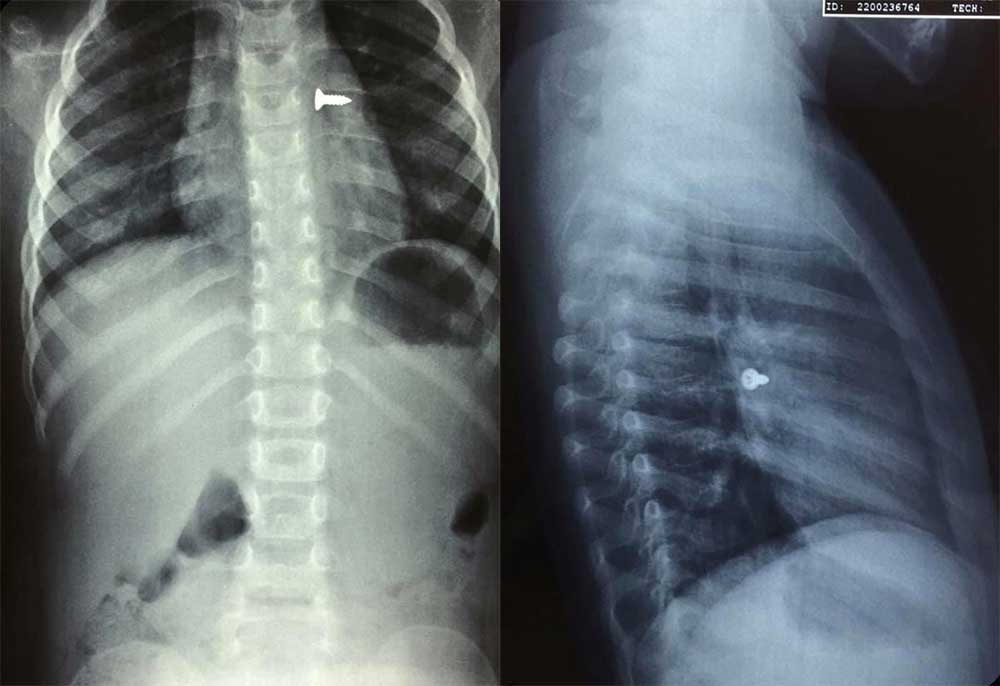

Σοκ προκαλούν οι ακτινογραφίες από ένα κοριτσάκι που κατάπιε βίδα, η οποία κατέληξε στον αριστερό του πνεύμονα.

Αμέσως του έγιναν ακτινογραφίες που έδειξαν πως η βίδα βρισκόταν στον αριστερό πνεύμονα του παιδιού.

Οι γιατροί άμεσα οδήγησαν το κορίτσι στο χειρουργείο και μετά από αρκετή ώρα κατάφεραν να αφαιρέσουν την βίδα.